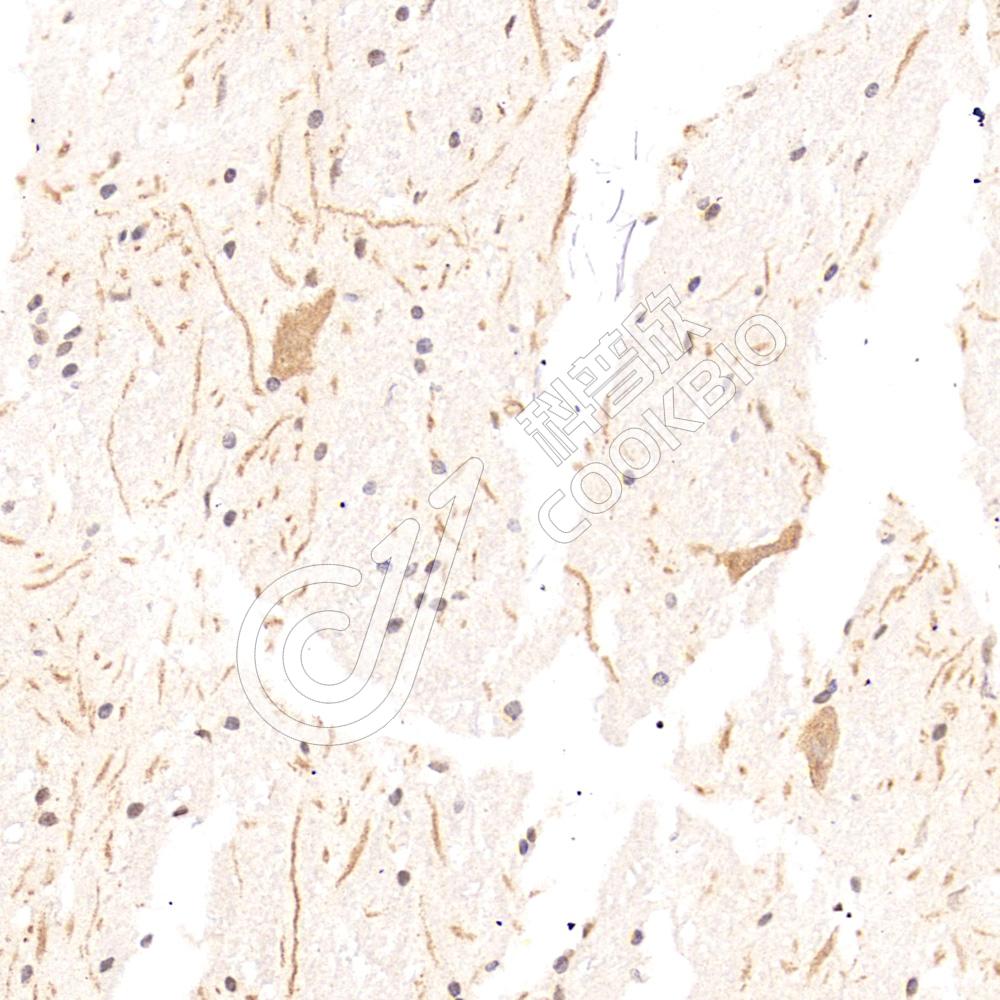

IHC检测GABA Transporter 3/GAT 3蛋白(货号 K1345327).

样品: 小鼠脊髓, 4%多聚甲醛 (货号KSG1101) 固定12-24小时.

抗原修复: Tris-EDTA抗原修复液(pH 9.0) (KSG1203), 98℃, 20分钟.

—抗: 1: 1300稀释, 4℃ 孵育过夜.

二抗: S-vision免疫组化多聚二抗(山羊抗兔),即用型 (货号KB3906), 室温孵育20分钟.